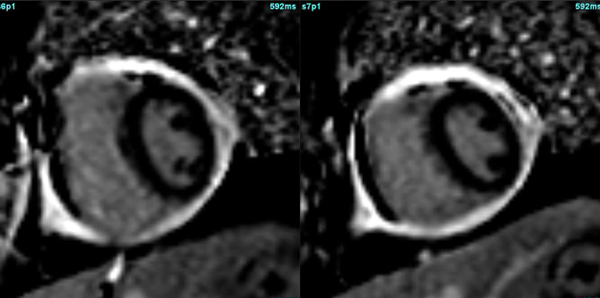

A common clinical presentation of LBBB induced cardiomyopathy is described in this post. It is always dilemma that if LBBB is cause or effect of dilated cardiomyopathy. However CMR can help in differentiating it from other causes and also in predicting response to device therapy. Utilise CMR to the fullest.